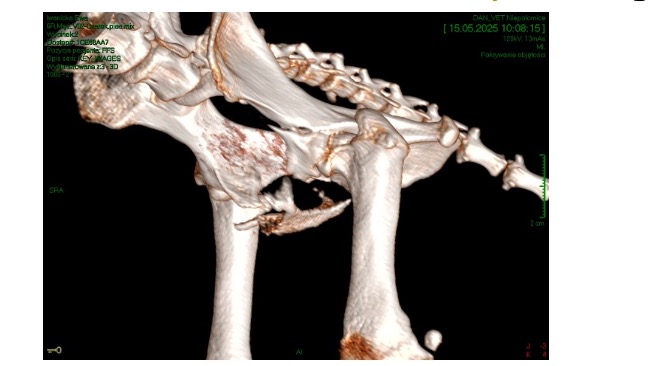

Als es scheindass sich sein Gesundheitszustand endlich stabilisiert, hatte Czaruś ein Unfall. Letzten Sonntag wurde er von einem Auto angefahren. Er wurde notfallmaßig in eine Tierklinik gebracht wo er noch am selben Tag zwiemal untersucht und diagnostiziert wurde. Er wurde außerdem am eine spezialisierte ortopedische Klinik überweisen - er hat bereits eine konsultation bei einem wunderbaren Tierarzt der Klinik Dr Hau erhalten. Leider erlitt Czaruś schwere Fakturen im Beckenbereich - Brüche des Schambeins, des sitzbeins , der linken Hüftpfanne sowie eine Bruch und Riss des linken Oberschenkelknochens.